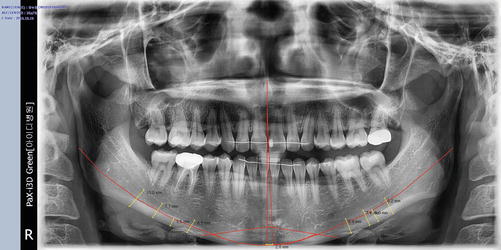

The amount of narrowing and lateralization (considering the degree of asymmetry) and the amount of angle and inferior border resection are determined after checking the course of the inferior alveolar nerve. Panoramic view is helpful in determining the amount of ostectomy of the mandibular angle and body, as well as the position of its ostectomy line (Fig. 5.4).